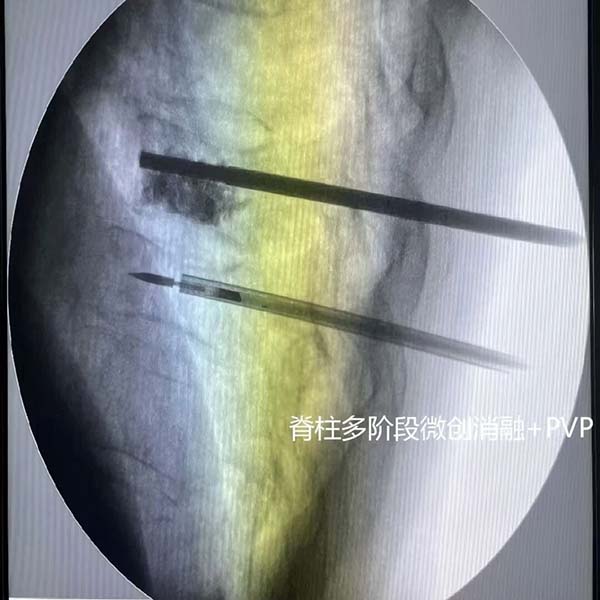

微创治疗减痛增效:针对脊柱及四肢转移癌,大力推行微创经皮椎体成形术(PVP/PKP)、微波消融技术,凭借创伤小、恢复快、止痛效果显著的优势,让无数饱受疼痛折磨的患者缓解病痛、重新站立;同步开展髋臼转移瘤“三脚架”技术,持续拓展微创治疗边界。

践行对口援疆使命:在“晋江携手影领未来”学术会议中,科室关哲医师成功演示椎体PVP技术,填补了新疆生产建设兵团第六师医院骨转移癌微创诊疗领域的技术空白。